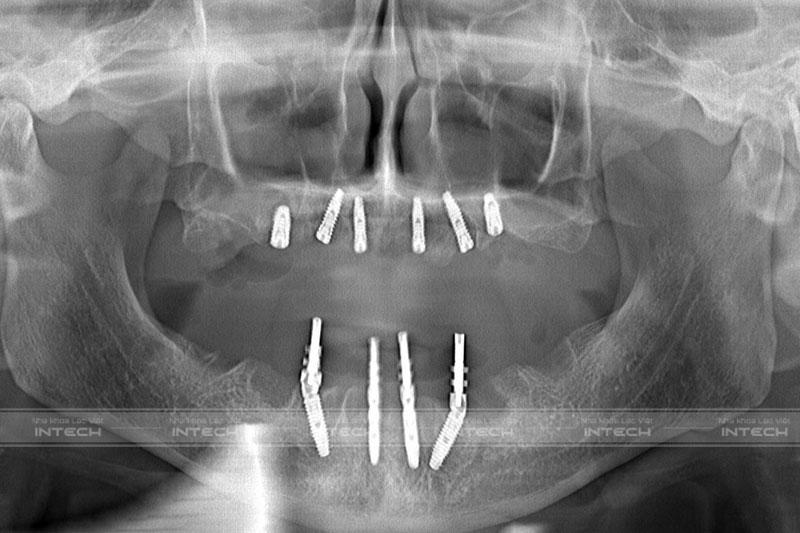

Dưới đây là hình ảnh phim X-quang của chú Tính sau khi trồng 6 trụ Implant hàm trên và 4 trụ Implant hàm dưới.

Kết quả sau khi cấy ghép Implant của chú Nguyễn Đức TínhKết quả sau khi cấy ghép Implant của chú Nguyễn Đức Tính

Có thể thấy rằng trụ Implant được cấy chính xác tại những vị trí xương hàm tốt nhất, tránh được các cấu trúc giải phẫu quan trọng. Đặc biệt, trụ Implant tích hợp ổn định vững chắc trong xương hàm sau khi cấy ghép.